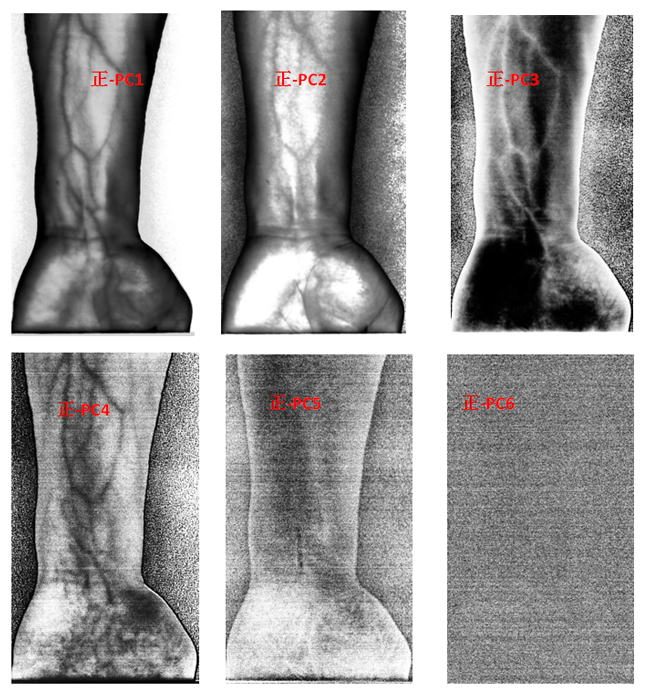

為了客觀地識別手臂上的靜脈,對經(jīng)預處理后的高光譜數(shù)據(jù)進行主成分分析(Principal Component Analysis, PCA),去除波段之間的多余信息、將多波段的圖像信息壓縮到比原波段更有效的少數(shù)幾個轉換波段下。圖9為手臂正反面經(jīng)PCA變換后的前6個主成分。

圖9 手臂正反兩面PCA處理后的前6個主成分